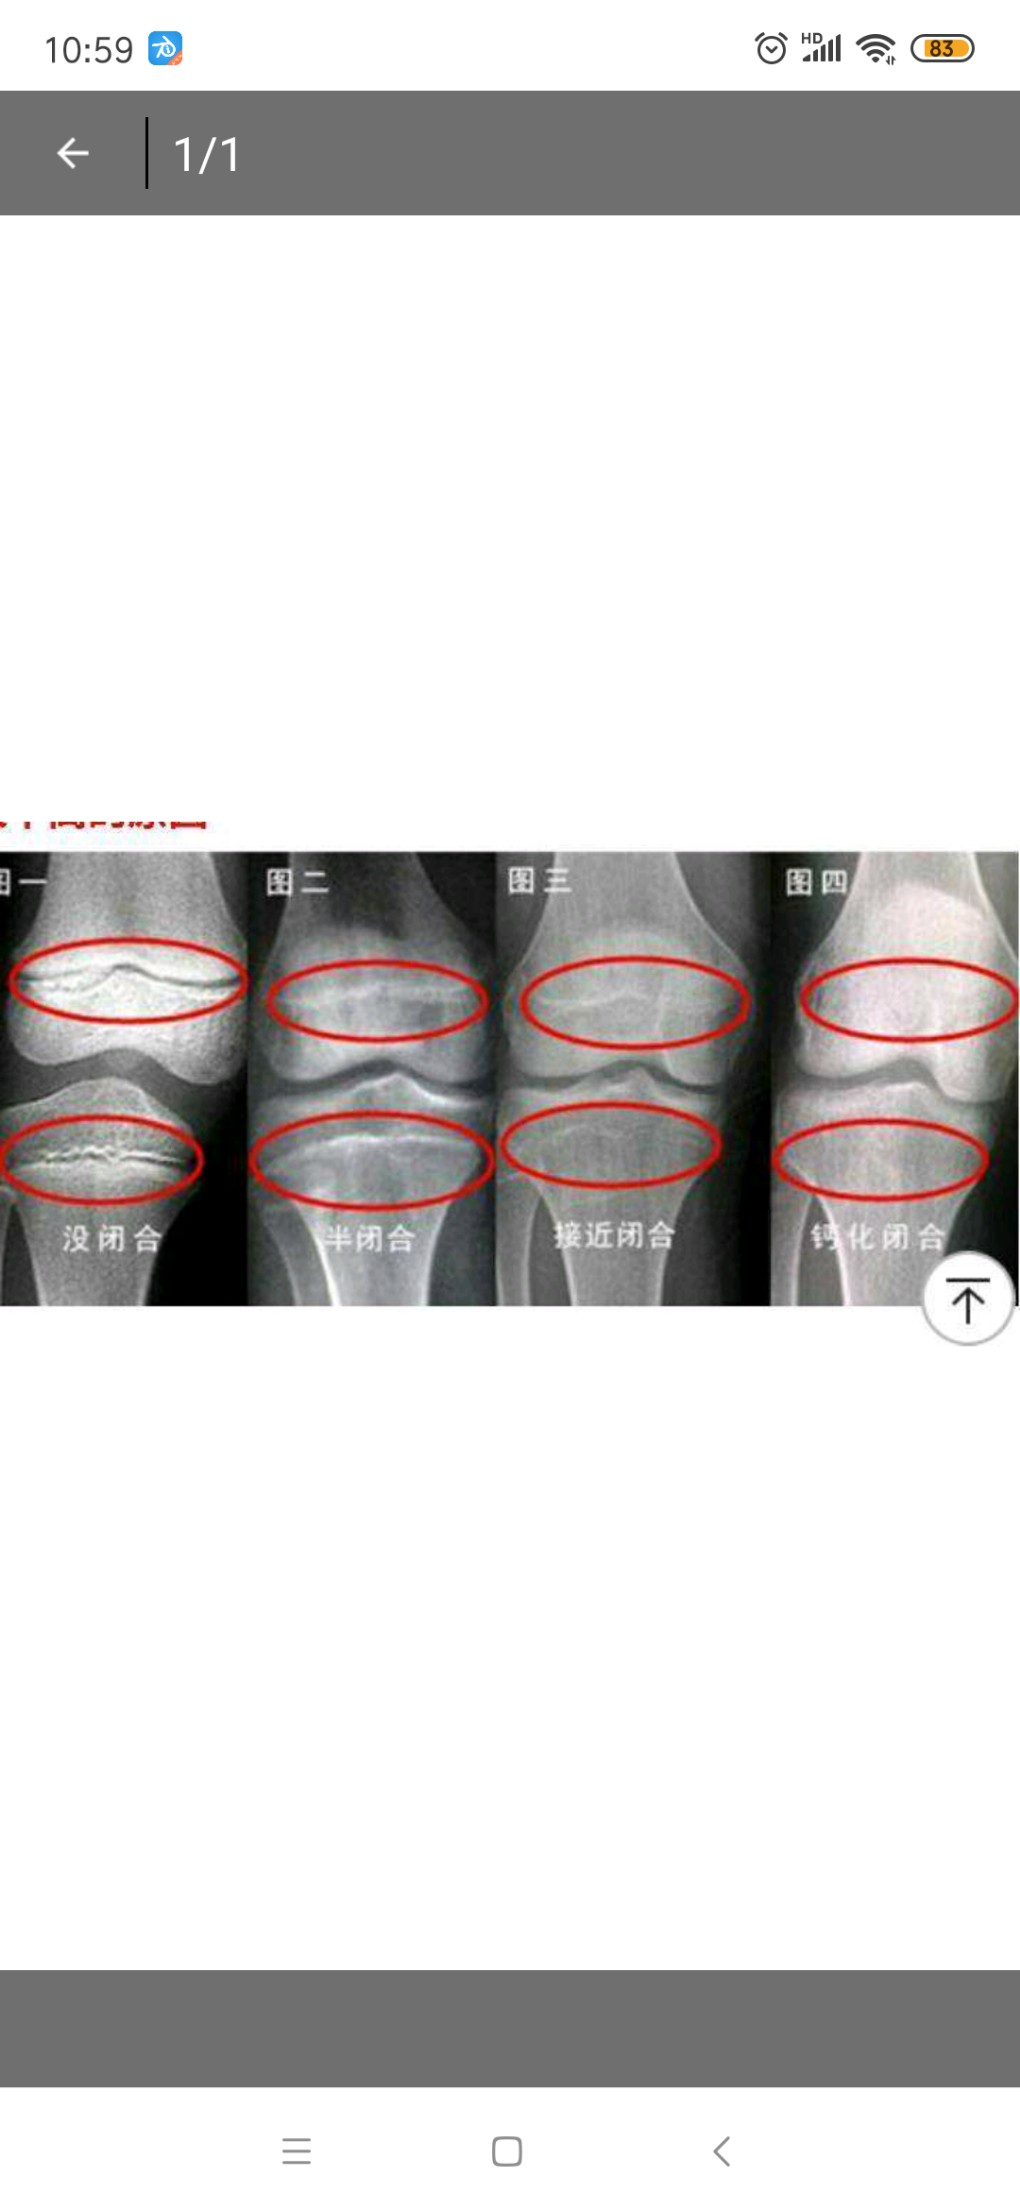

这是我的X光片,看看骨骺线有没闭合???

楼主在询问专家关于骨骺线是否闭合的问题楼主提供的图片不够清晰,片子上面有一条明显的白线,但在照片上仅能模糊地看到根据百科上的资料,骨骺线是幼儿X光片上显示的一条较宽的透光带,代表骨骺与干骺端之间的软骨随着年龄增长,骨...